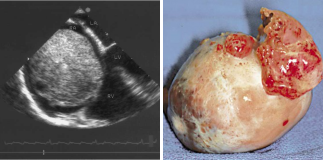

心臟彩超及食道超聲可見(jiàn)右房?jī)?nèi)囊性占位病變;室間隔及左室壁厚度正常高限;雙房大; 左室收縮功能正常; 彩色血流示: 各瓣膜未見(jiàn)病理性返流。

腫瘤病理結(jié)果與CT檢查顯示的大小、 形態(tài)相符合。